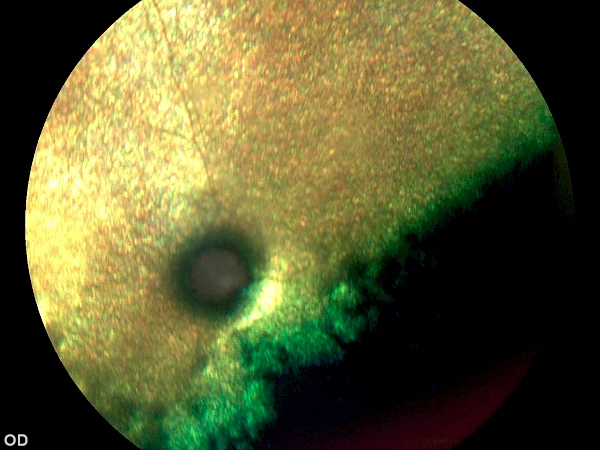

Limbales Melanom vor Operation Limbales Melanom vor Operation

nach Operation nach Operation

1 Jahr nach Operation 1 Jahr nach Operation